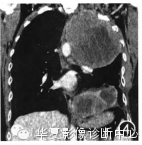

术后4个月肿瘤复发,胸部CT增强(图4)示左侧胸腔内多发混杂密度占位,肿块呈明显不均匀、厚环状强化,左侧胸膜、心包、肋骨及胸壁均见侵犯。

图4术后4个月肿瘤复发,CT增强示左侧胸腔内多发、巨大囊实性占位,侵犯邻近胸膜、心包、肋骨及胸壁